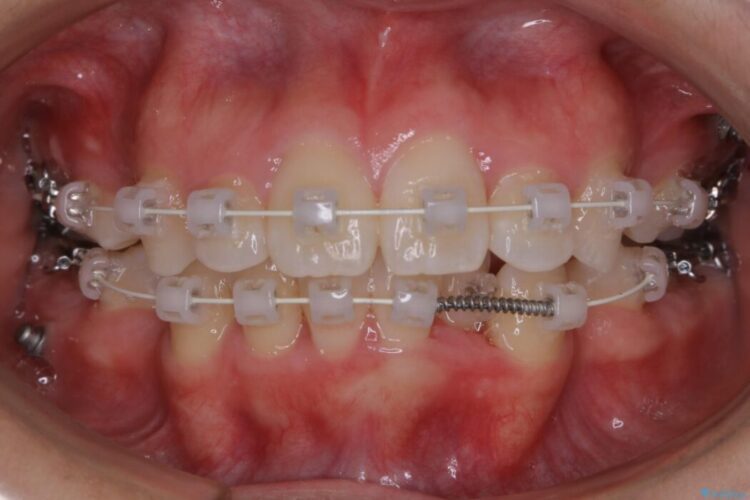

- 矯正装置:ワイヤー(審美装置)

検査したところ歯に対して骨が上顎・下顎共に小さいことがわかりました。

それによりスペースが少なく歯列がガタついたり前方傾斜する生え方となっていました。

よって本症例では抜歯により歯の本数を減らすことにより整えるスペースを確保してワイヤー装置にて歯列矯正を行うこととしました。

本症例の患者様は顎の骨が小さく歯をきれいに並べるための隙間がないため、歯が重なったり傾斜してしまっていました。

抜歯を行うことによりスペースを確保し、小さい骨幅でも歯並びを整えることができます。